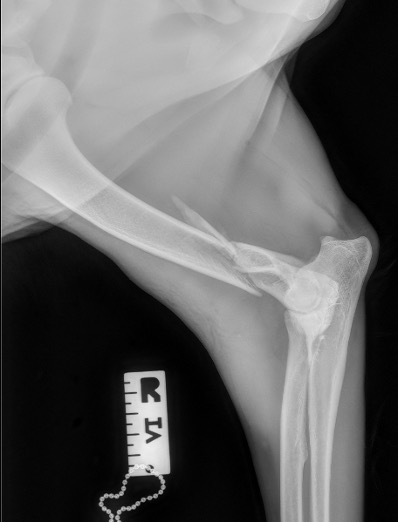

Exemple 2 :

Figure 4 : Pré-Op